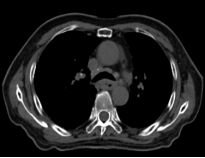

Before Photon Radiotherapy Before Carbon Ion Radiotherapy After Carbon Ion Radiotherapy 1 Month After CarboRadiotherapy

Before Photon Radiotherapy Before Carbon Ion Radiotherapy After Carbon Ion Radiotherapy